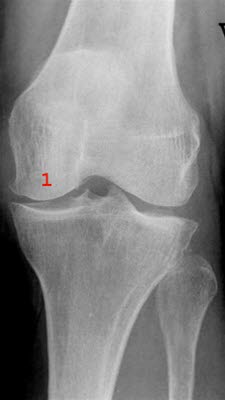

Gonartrose, lett

Lett redusert bruskhøyde medialt i kneleddet med små påleiringer på mediale femurcondyl (1)